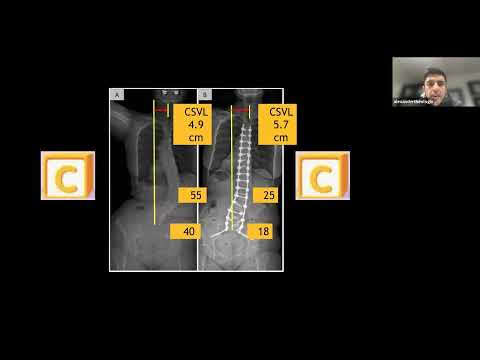

Coronal Alignment in Adult Spinal Deformity : Alekos Theologis, MD - March 10, 2023